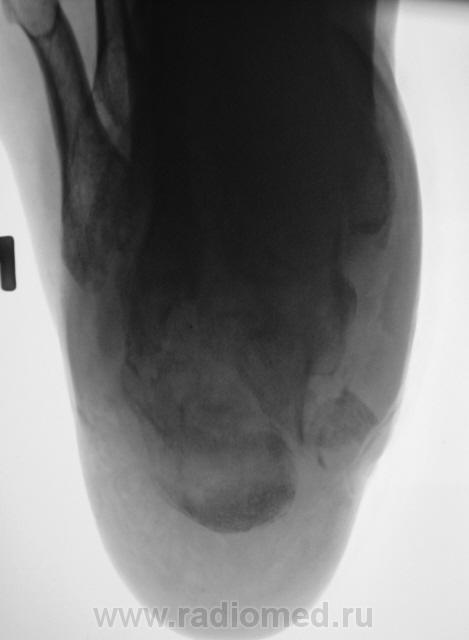

Лечение состояло из "множества рентгенов" и гипса. Срок - 5 месяцев.

Сейчас думают об остеомиелите.

Контуры пяточной кости относительно четкие, разрежение структуры пяточного бугра, в проекции перелома уплотнение структуры кости( имею в виду последние снимки).Клиника остеомиелита есть?

Клиники остеомиелита, с моей точки зрения, нет.

А что Вы в протоколе написали?Я тоже не вижу остеомиелита.

Во-первых, деформация пяточной кости; во-вторых, отсутствие консолидации, через некоторое время и ложный сустав сформируется. Неоднородное уплотнение костной структуры в теле кости может быть обусловдено как остеомиелитом, так и перераспределением нагрузки.

Признаков остеомиелита не вижу, только консолидир перелом с неуд стоянием отломков.